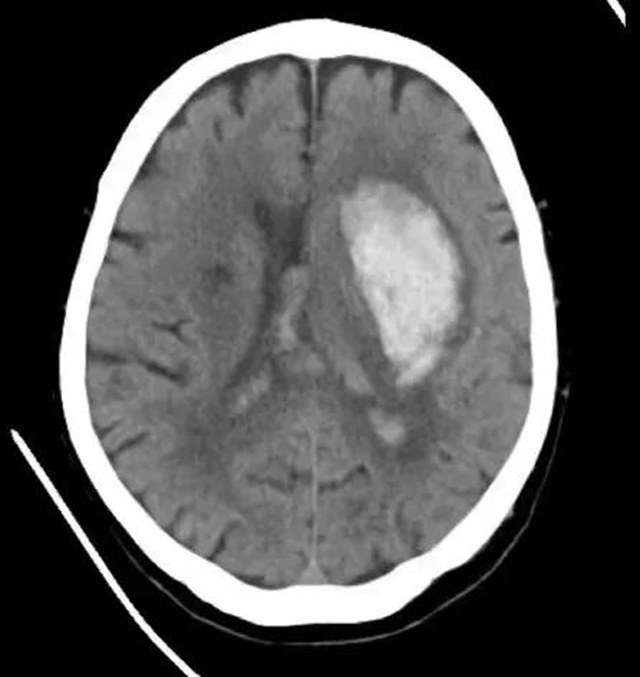

12月11日,余婆婆在家中突发头痛、呕吐,随即出现昏迷,家属赶紧将她送到西南医科大学附属医院(康健中心院区)抢救。急诊CT提示为左侧基底节区高血压性脑出血,出血量高达约60ml,更为不利的是,此时,余婆婆的新冠病毒核酸检测结果显示阳性。

术前术后影像对比

“最有效的处理措施,就是通过清除脑内血肿、降低颅内压。”在陈礼刚教授的统筹协调下,神经外科积极完善术前准备。12月11日,在主刀医生(李慎杰、田俊杰)、手术室医护人员(李青青、莫舻)、麻醉科医生(刘清湄、代俊超)的密切配合下为患者完成了急诊微创颅内血肿清除手术。术后复查颅内血肿清除满意,术后次日患者就已苏醒,并能单独完成睁眼闭眼、抬手、握手、牵铺盖等动作。